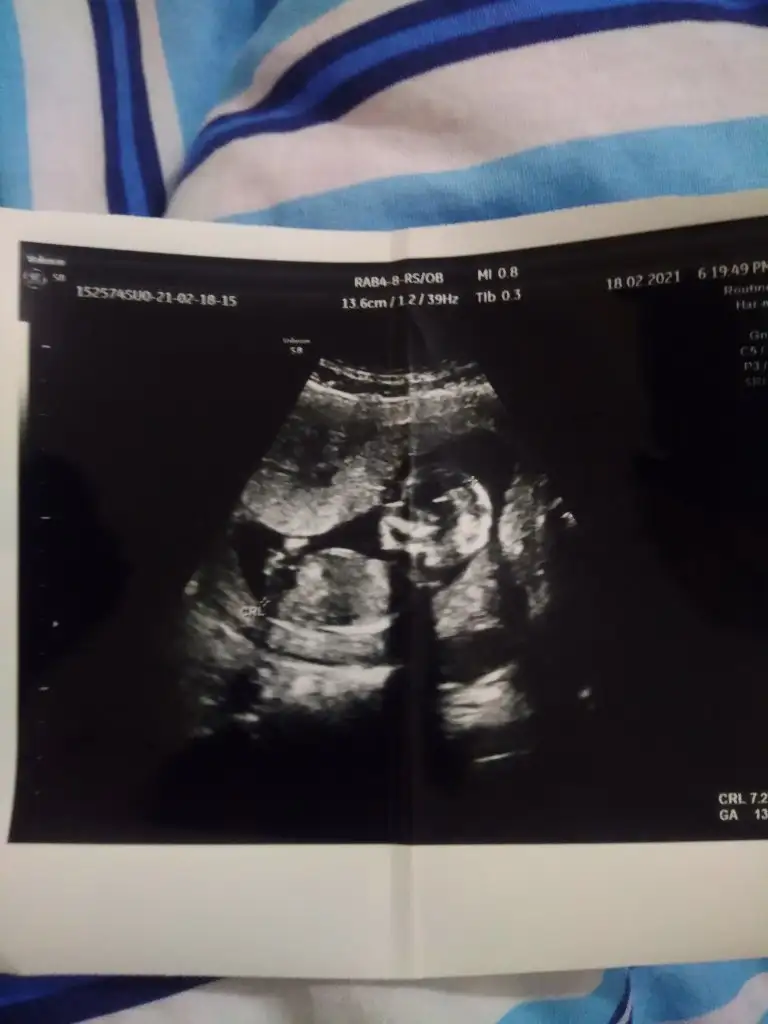

Benimde tahmin edebilir misiniz ilk resim 6 +4 günlük ikinci resim 13 +3

• IMG_20210218_232405.webp

21,5 KB · Görüntüleme: 87